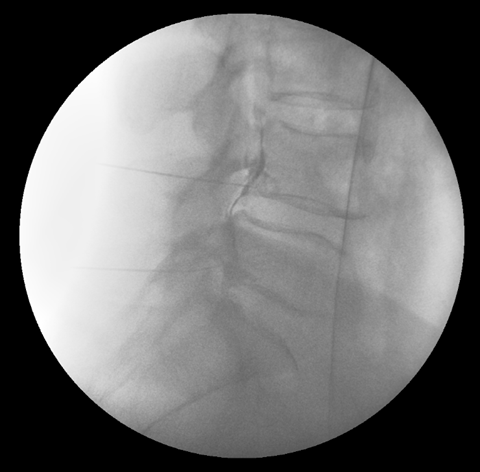

그림4.png 촬영 일시: 2025.05.02

<Fig 1. 여러마디 허리디스크로 진단된 MRI>

허리 3-4번, 4-5번, 5-6번에 걸쳐서

디스크 탈출증이 확인되었거든요.

특히 4-5번 디스크의 탈출 정도가 심했는데

이것이 바로 환자분이 겪고 있던

오른쪽 엉덩이 옆 통증, 밑 통증, 위 통증의

진짜 원인이었습니다.